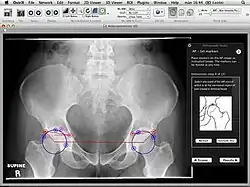

Orthopaedic Studio is an application designed to help orthopaedic specialists perform several common quantitative hip examinations that are based on standard x-ray images.

The application is implemented as a plugin for the medical image viewer OsiriX and thereby only runs on Mac OS X.

Orthopaedic Studio evaluates four different types of hip radiographs (standing anteroposterior, Von Rosen, false profile and frog). On such images a number of standardized angles, offsets and ratios can be measured, including:[1]